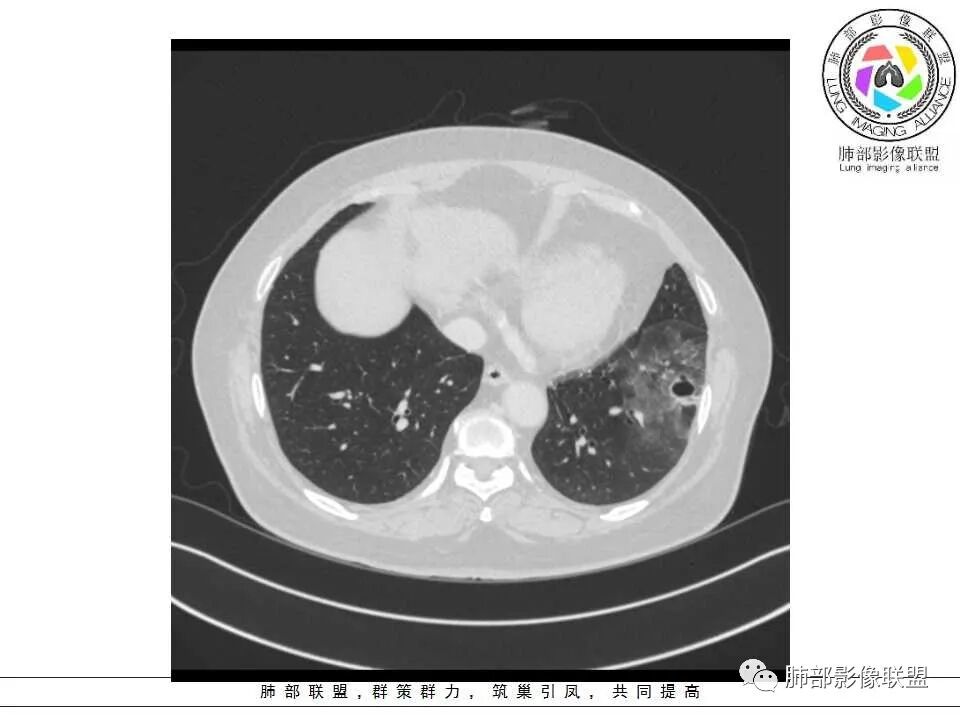

女性,65岁,左肺下叶空腔边缘见不规则结节,结节强化轻、不均匀,局部坏死边界较清楚,胸膜为糊墙为主,膈面胸膜判断不清楚似有结节;空腔内见分隔,或者数个融合,局部张力稍弱,边缘见支气管截断和血管集束;外周见大片磨玻璃影,部分边界模糊。结合病史炎症肯定有,但是囊腔结节这部分感觉恶性征象多过良性,考虑囊腔型腺癌可能性大,鉴别肺大疱感染

左肺下叶外侧基底段空洞,壁增厚,轻度强化,周围磨玻璃影,边界清晰,考虑囊腔型肺癌。

女性,65岁,咳嗽、咳痰2月余,伴发热数日。

胸CT:左肺下叶囊腔,壁厚薄不均,可见壁结节,囊腔内可见断裂小梁,部分融合,周围边界较清楚GGO,胸膜牵拉,可见血管集束、支气管充气征,冠状位部分层面可见支气管在囊腔边缘截断。考虑:囊腔型腺Ca。鉴别:肺大疱感染,CPAM等。

1、左肺下叶外基底段不规则囊腔样病灶,囊腔内有条形影及血管穿行。

2、囊壁薄厚不均匀,稍显僵硬,有壁结节(对应边缘分叶等)、结节强化明显。

3、灶周环以大范围磨玻璃影,非常均匀,没有重力分布趋势,分叶状,边界隐约可变。

4、冠状位部分层面可见支气管在囊腔边缘截断。